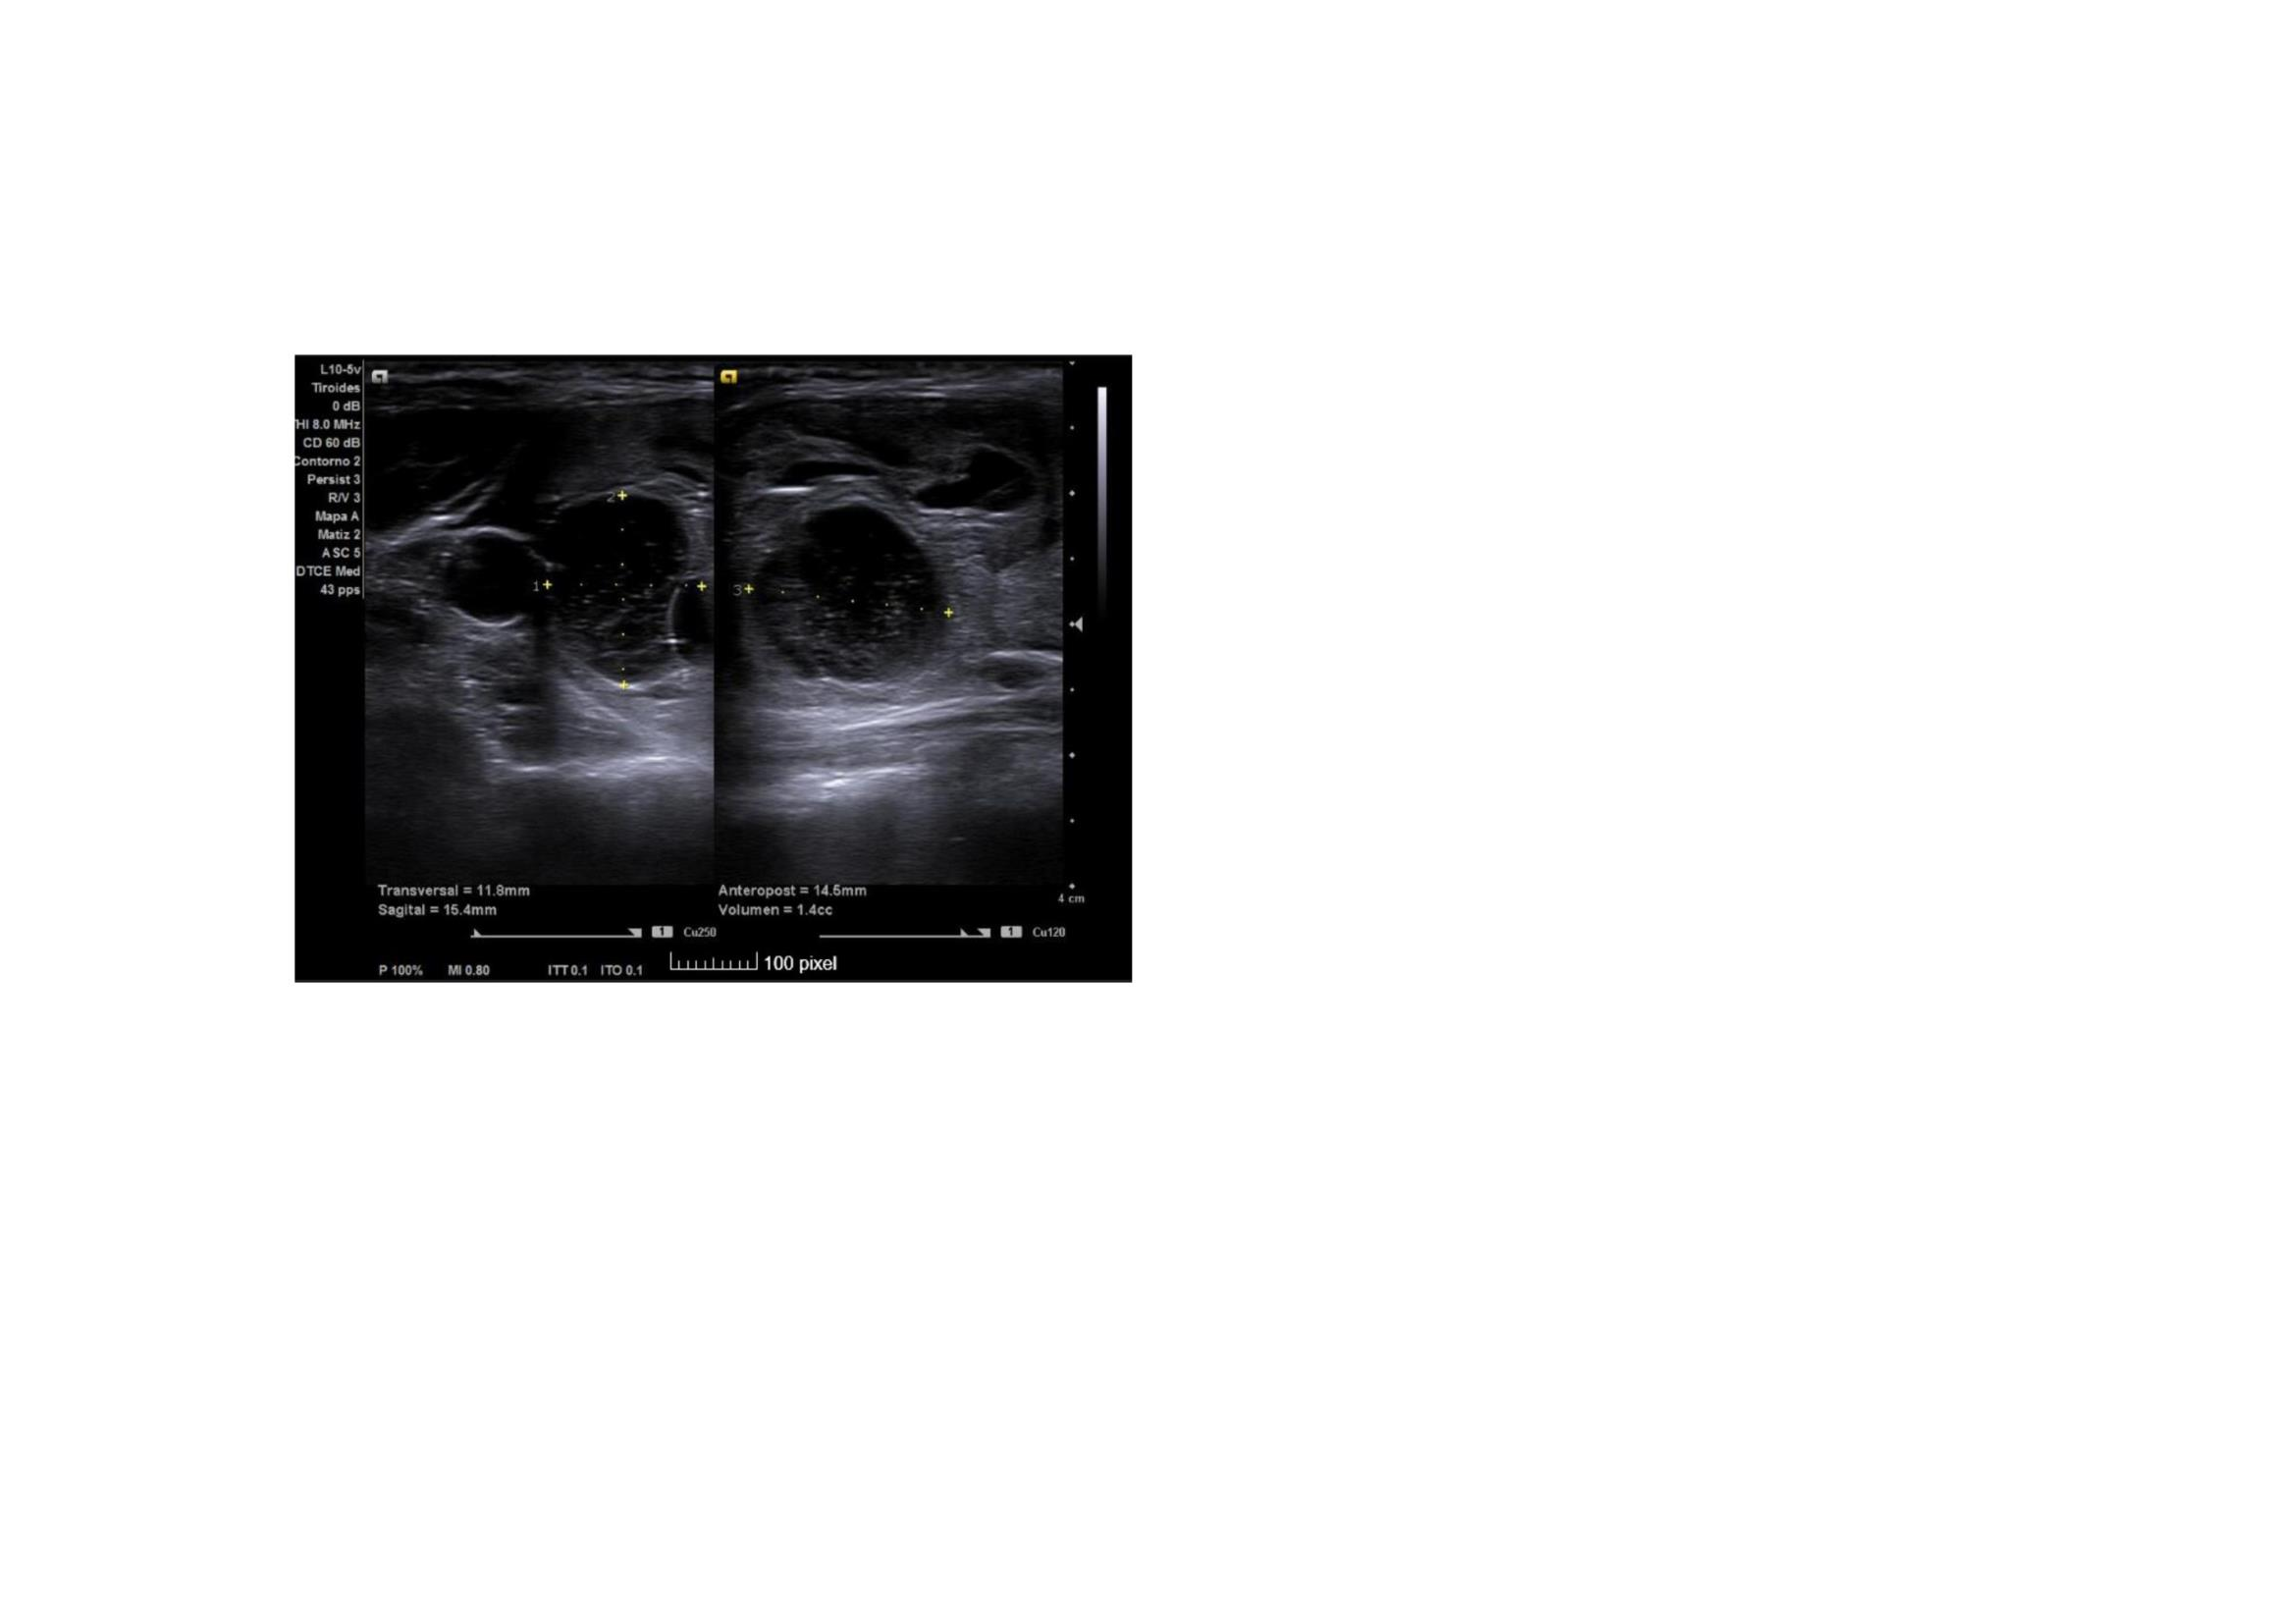

Ecografía clínica: En lóbulo tiroideo derecho observamos nódulo mixto sólido-quístico, de 11,8 x 14,5 x 15,4 mm, de bordes bien delimitados mayoritariamente hipoecogénico, parcialmente tabicado a nivel inferomedial, más alto que ancho con micro calcificaciones en su interior. TIRADS 5.